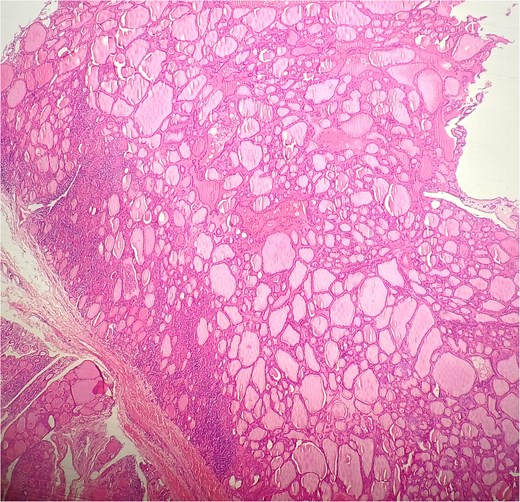

A 47-year-old woman with unremarkable medical history, presented with a 2 months history of neck mass along the midline. Physical examination revealed a 6 cm mobile, thyroid nodule without compressive symptoms. There was no associated erythema, fluctuance, tenderness or adhesion to adjacent structures. There was also no associated cervical lymphadenopathy. The rest of the physical exam was unremarkable. Laboratory tests including TSH, FT3, and FT4 revealed normal levels. On cervical ultrasound, there were a 62 mm left toto-lobar nodule classified as EU-TIRADS3, and an 11 mm right nodule, also classified as EU-TIRADS3. Fine-needle aspiration cytology concluded to a benign lesion classified as BETHESDA II. The patient reported respiratory discomfort in the supine position, leading to the indication for a lobectomy. Gross examination of the specimen revealed a toto-lobular nodule with a colloid appearance. It was well-circumscribed by a thin and regular fibrous capsule. The nodule measured 4 × 6 cm and exhibited areas of fibrous, whitish remodeling, as well as hemorrhagic and cystic changes. On microscopic examination, the nodule corresponded to a macro vesicular adenoma altered by fibrosis and hemorrhage. It was surrounded by a thin, regular, and intact fibrous capsule. However, at the periphery of the nodule, adjacent to the thyroid pseudo capsule, a 1.2 cm cystic ductal structure was observed. It showed pseudostratified ciliated columnar and squamous epithelial lining associated with thyroid follicles in the surrounding stroma (Figs 1 and 2). These thyroid follicles were bland with no papillary nuclear atypia or invasion (Fig. 3). The cyst was filled with a thin eosinophilic material (Fig. 4) Lymphocytic thyroiditis of mild severity was identified in the rest of the thyroid tissue. Based on these findings, the diagnosis of macro vesicular thyroid adenoma with ITTGDC and lymphocytic thyroiditis was made. After the surgery, the patient developed temporary dysphonia.

HE × 4 incidental finding of cystic duct structure in the adjacent thyroid gland tissue.